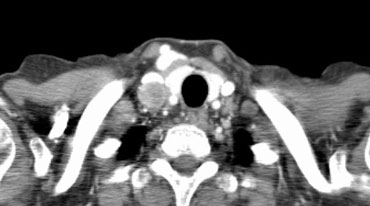

Hình ảnh của một bệnh nhân có khối u bên phải.

Có các hạch N3 ở phía đối bên và ở vùng thượng đòn phải.

Cuộn qua các hình ảnh để xem.